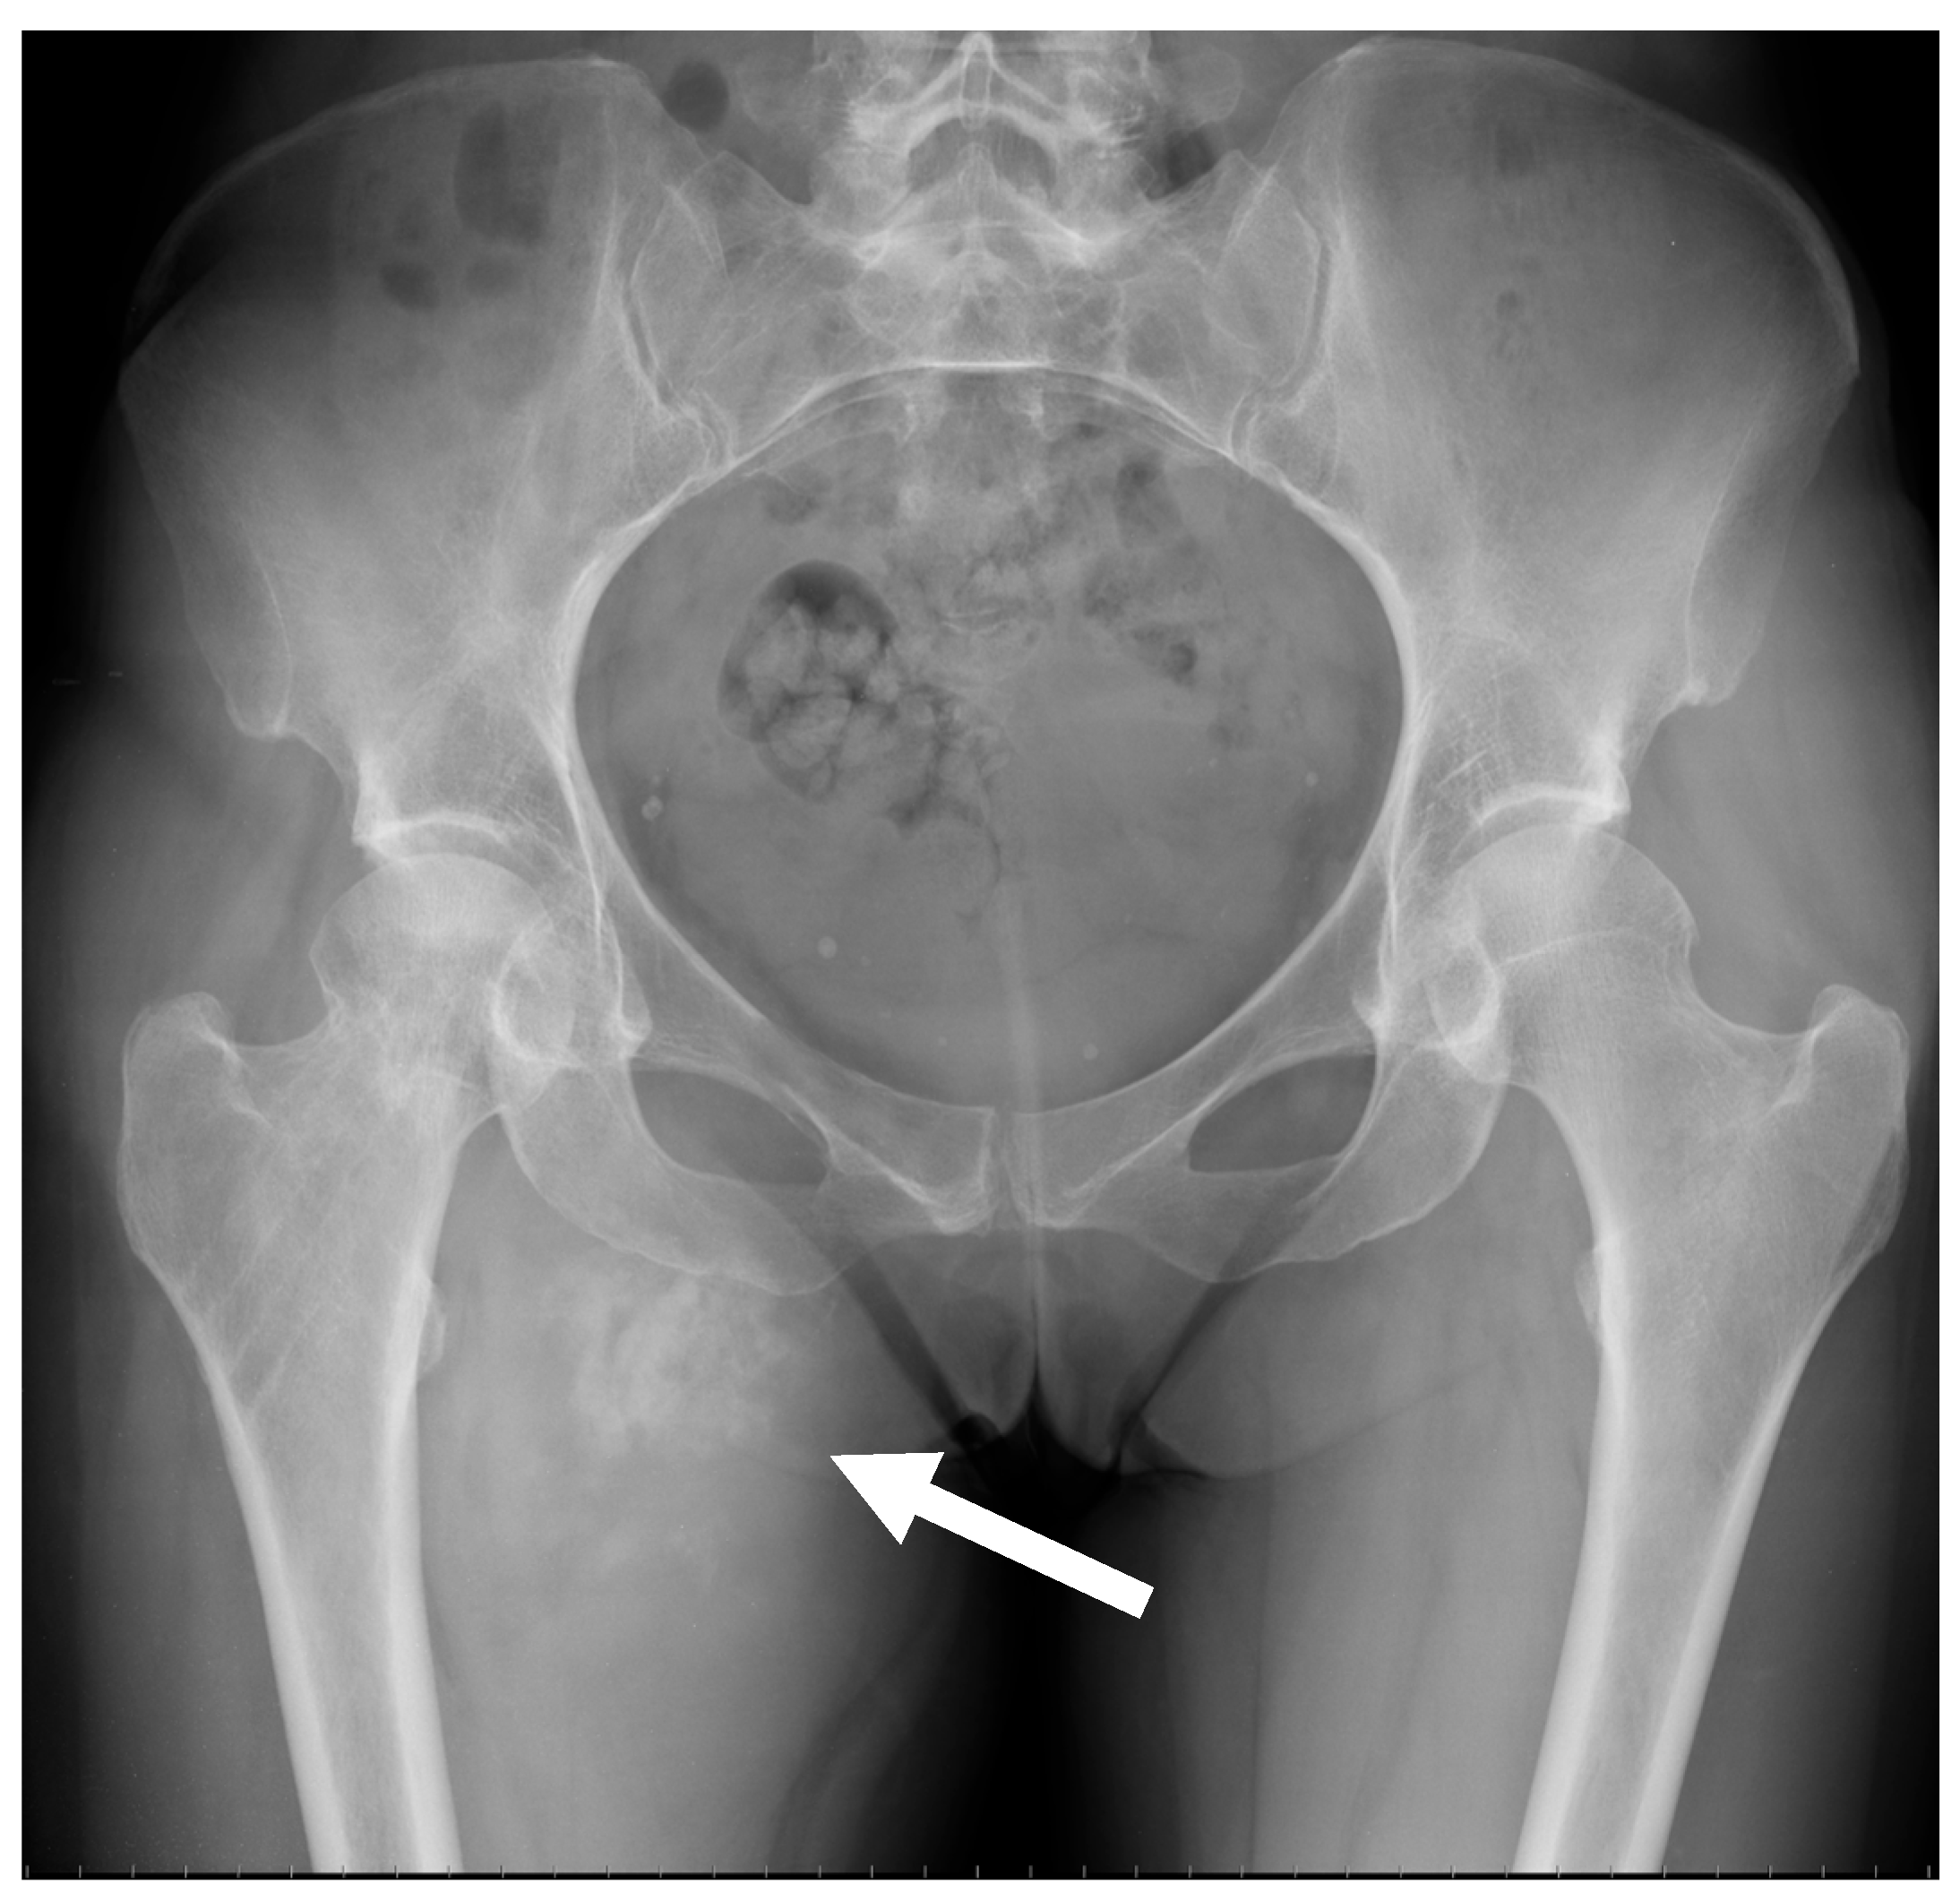

2.2. Radiological Findings on Conventional Radiographs

| Conventional osteosarcoma | Mixed (lytic and sclerotic) or completely eburneous | Sunburst, Codman triangle, other irregular/aggressive types | Soft-tissue components frequently displayed |